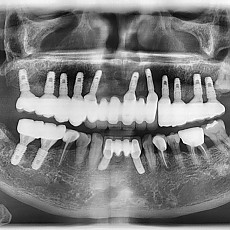

시술전후사진 2 페이지

Total 62건 2 페이지